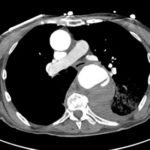

The patient’schest X-ray revealed a prominent mediastinum and opacification in the left middle and lower lung fields. The CT showed an aortic aneurysm extending from the thorax to the abdomen with rupture near T7 (blue arrow). It also showed periaortic hemorrhage with active extravasation (green arrow) likely secondary to a penetrating ulcer and bilateral pulmonary opacities concerning for hemothorax (pink arrow).